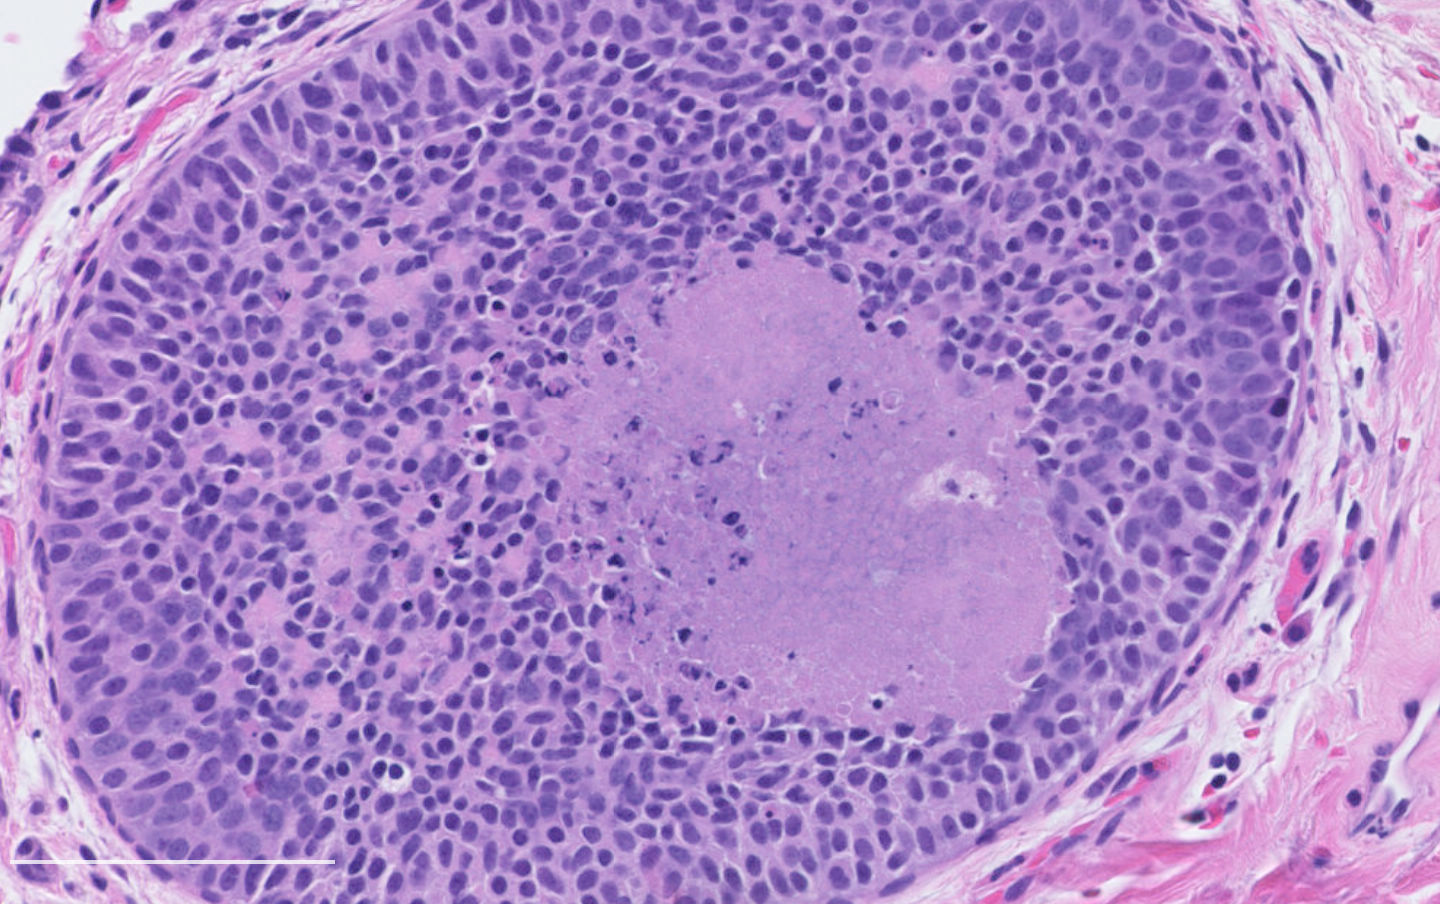

- Diagnostic criteria:

- Neuroendocrine morphology with 2 - 10 mitoses per 2 mm² or presence of necrosis

- Necrosis can be in large zones but is usually punctate

- Neuroendocrine morphology with 2 - 10 mitoses per 2 mm² or presence of necrosis

- Neuroendocrine histologic patterns similar to typical carcinoids: organoid, trabecular, rosette formation, papillary, pseudoglandular, follicular

- Tumor cells are as typical carcinoid: uniform with a polygonal shape, round to oval nuclei with salt and pepper chromatin and inconspicuous nucleoli, along with moderate to abundant eosinophilic cytoplasm

- Greater pleomorphism than for typical carcinoid is common (Arch Pathol Lab Med 2010;134:1628)

- Stroma is fine and highly vascularized; hyalinization, cartilage or bone formation are possible

Contributed by Philippe Joubert, M.D., Ph.D.